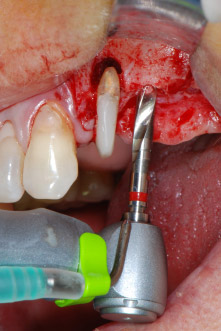

Имплантологичното ложе е подготвено в позиции 25 и 26 с ротиращи инструменти, използвайки обратен наконечник 20:1 с усъвършенстван и мощен имплантологичен мотор (Implantmed, W&H) (Фиг. 8).

Следващата препарация близо до синуса отново е извършена с пиезохирургичен накрайник (Piezomed, накрайник S2).

Предавателното съотношение20:1 заедно с високия въртящ момент до 6.2 Ncm осигуряват препарация на ниски обороти, поставяне на имплант и рязане. Финалната препарация близо до мембраната на синуса отново е извършена с пиезоелектрически апарат и накрайник със сферичен диамантен връх.